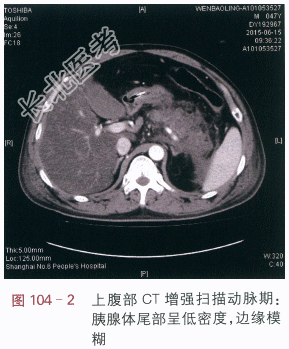

读片分析:CT平扫:胰腺体尾部肿胀,密度减低,边缘模糊,周边见流出影,左肾前筋膜肥厚(见图104-1)。附见:肝脏密度减低。CT增强扫描:胰腺体尾部呈低密度,边缘模糊,胰腺体部残留组织强化,尾部组织坏死无强化(见图104-2~图104-4)。